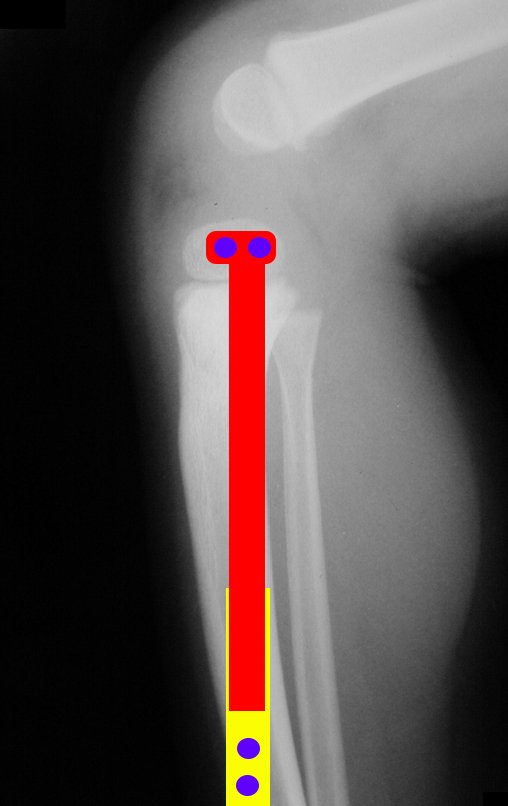

Ewing sarcoma of the tibia

In December 2006, the patient underwent surgery to resect the proximal metaphyseal segment of the tibia, including the growth plate, and self-transplantation of the growth cartilage of the proximal segment of the fibula, through transfer to the tibia, without microsurgery.